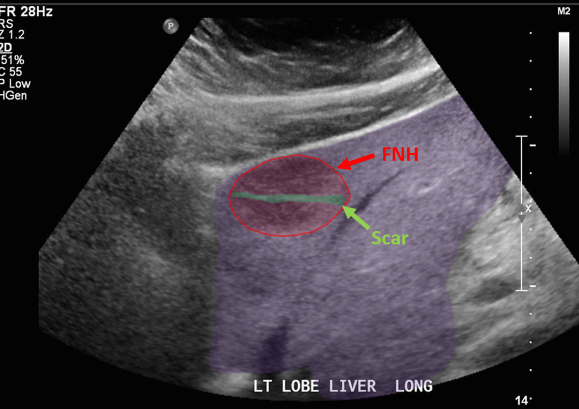

FNH의 경우 초음파소견은 다양하다. 병변은 등에코, 저에코, 고에코의 균질한 덩어리로 나타날 수 있다. 간내 혈관을 대체할 수 있는 대량 효과가 있다. 단지 18%의 사례에서만 중앙 흉터(저에코성 센터)가 존재한다. 이는 간혈관종과 매우 유사해 보인다. 또한 혈관 기형부위와 관련이 있다. 일반적으로 5cm 미만이다.

FNH (Focal Nodular hyperplasia) US finding

- hypoechoic lesion with central scar

위에서 보인 초음파소견처럼 FNH는 경계가 명확한 균일한 종괴이며 내부에 섬유성 반흔이 있다. 에코는 저에코를 갖지만 간혹 고에코나 등에코등 다양하게 나타날 수 있으며 피막이 없다. 도플러상 과혈관성을 보이며 정상 간세포조직을 갖는다. 초음파 만으로 간암과 구별할 수 없으므로 혈액검사, CT 와같이 다양한 검사를 통한 진단이 필요하다.